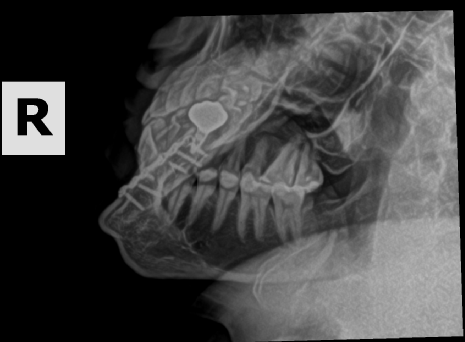

The story of how I got the x-ray or at least the whole scenario was kind of funny. I broke my pinky somehow at my friend's house in Oklahoma in the fall of 2023. When I went to the doctor they did an x-ray of my hand. I have a few metal parts in my head and then told them I got into a fight and thought I may have hurt some implants in my head. Not really but I just wanted these X-rays.